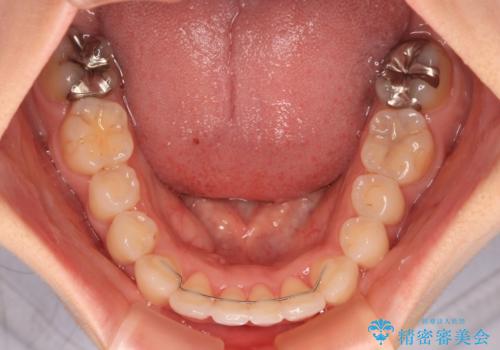

左右ともに、上顎第二大臼歯が欠損しており、下顎の第二大臼歯が十分に咬み合う歯がない状態のため、放置しておくと下顎の奥歯が挺出してくる可能性があります。

安定した咬み合わせを維持するためにも、将来的に上左右にインプラント補綴が必要となります。